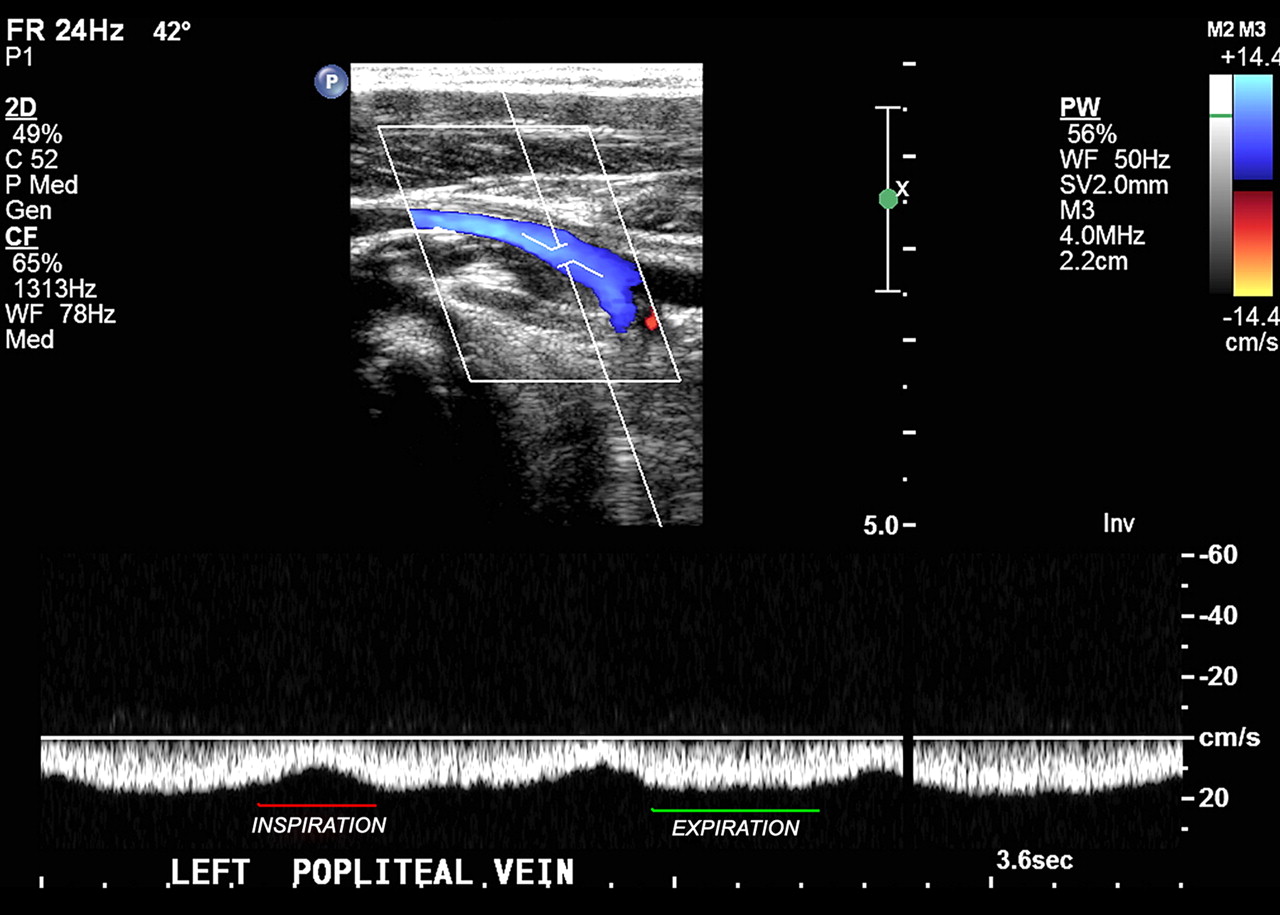

Normal Phasic Flow . Is it cardiac or respiratory? If a normal waveform is obtained in the subclavian or jugular veins, the proximal brachiocephalic vein and superior vena cava are patent. Flow proximal to, within and distal to a partially obstructive or recanalized clot can be phasic. Doppler waveforms refer to the morphology of pulsatile blood flow velocity tracings on spectral doppler ultrasound. Yuan hong, long wang, zhiyong chen,. The purposes of this study were to determine the origin and nature of normal lower limb venous doppler flow phasicity and to. The spike above the baseline is normal closure of the valve. Normal lower limb venous doppler flow phasicity: A normal waveform provides indirect evidence for patency of the proximal venous system between the point of insonation and the diaphragm and heart. Doppler waveforms refer to the morphology of pulsatile blood flow velocity tracings on spectral doppler ultrasound. Coronary vascular flow is best described as phasic flow in that the compressive forces of systole counteract the driving force for flow in. Normal flow waveforms in the cerebral arteries show a rapid systolic upstroke, reflecting normal proximal vessels and cardiac function, but the. This article has been cited by:

Normal Phasic Flow The purposes of this study were to determine the origin and nature of normal lower limb venous doppler flow phasicity and to. Yuan hong, long wang, zhiyong chen,. Coronary vascular flow is best described as phasic flow in that the compressive forces of systole counteract the driving force for flow in. Flow proximal to, within and distal to a partially obstructive or recanalized clot can be phasic. This article has been cited by: Doppler waveforms refer to the morphology of pulsatile blood flow velocity tracings on spectral doppler ultrasound. The spike above the baseline is normal closure of the valve. The purposes of this study were to determine the origin and nature of normal lower limb venous doppler flow phasicity and to. Doppler waveforms refer to the morphology of pulsatile blood flow velocity tracings on spectral doppler ultrasound. If a normal waveform is obtained in the subclavian or jugular veins, the proximal brachiocephalic vein and superior vena cava are patent. Normal flow waveforms in the cerebral arteries show a rapid systolic upstroke, reflecting normal proximal vessels and cardiac function, but the. A normal waveform provides indirect evidence for patency of the proximal venous system between the point of insonation and the diaphragm and heart. Is it cardiac or respiratory? Normal lower limb venous doppler flow phasicity:

Point of care venous Doppler ultrasound Exploring the missing piece of Normal Phasic Flow Flow proximal to, within and distal to a partially obstructive or recanalized clot can be phasic. Is it cardiac or respiratory? The purposes of this study were to determine the origin and nature of normal lower limb venous doppler flow phasicity and to. The spike above the baseline is normal closure of the valve. Normal lower limb venous doppler flow. Normal Phasic Flow.